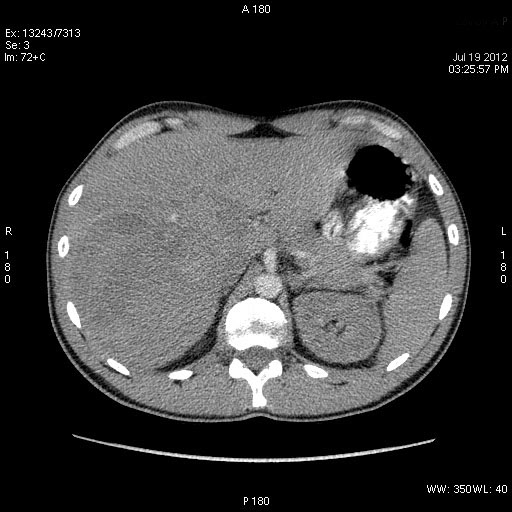

Молодой человек, наркоман, поступил в хирургическое отделение с подозрением на абсцесс печени.

Жалобы на высокую температуру, слабость.

Сонограмма печени:

Год назад при УЗИ в печени находили образование больших размеров.

КТ через день

Что-то не укладывается именно ультразвуковая картирка в абсцесс печени.

После КТ хирурги заказали дренирование "абсцесса".

Выполнена диагностическая пункция из 4х участков, получена только кровь.